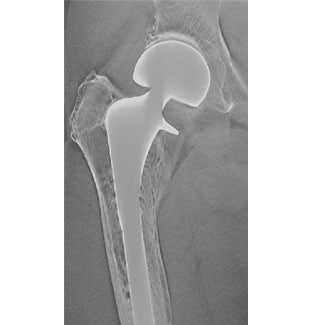

Artificial joint replacement support

The quality of life of an arthralgia patient has been dramatically improved by artificial joint replacement. T-smart (Tomosynthesis-Shimadzu Metal Artifact Reduction Technology) on our fluoroscopy system and general radiography system provides enhanced tomographic images by suppressing the artifacts around the metal objects even further. This application greatly helps in follow-up replacement surgeries, as it precisely enables diagnoses of the boundary between bone and implant.

Follow up of after BHA (Bipolar Hip Arthroplasty ) (Courtesy of Kanazawa University Hospital, Japan )